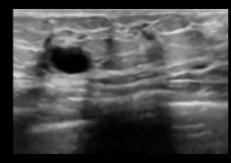

The method's implementation is tested on ten random BUS images. Various denoising filters were used, including Wiener filter without Fast Fourier Transform (FFT),WienerwithFFT,Meanfilter,Medianfilter,Bilateral filter, Anisotropic Diffusion filter and Total Variation filter with the outcome indicating that the proposed method for specklenoisereductionoutperformsallothers.

applyingMeanFilter,theresultisshowninFigure2(d).The outcome of the Median Filter is shown in Fig 2(e). Figure 2(f) depicts the outcome of using the Bilateral filter, while Figure 2(g) depicts the result of using the Anisotropic Diffusion filter, Figure 2(h) portraits the result of Total Variation filter and Figure 2(i) shows the result of NLM filter.

TheoriginalBUSimageisdisplayedinFigure2(a). The output of a Wiener Filter without FFT is shown in Figure2(b),whichusesa3x3kernel.Theresultofapplying the Wiener filter with FFT is shown in Figure 2(c). After

(a) (b) (c) (d) (e) (f) (g) (h) (i) Fig2.(a)Original BUSimage (d)MeanFilter (g)Anisotropic DiffusionFilter (b)WienerFilter withoutFFT (e)MedianFilter (h)TVFilter (c)WienerFilter withFFT (f)BilateralFilter (i)NLMFilter